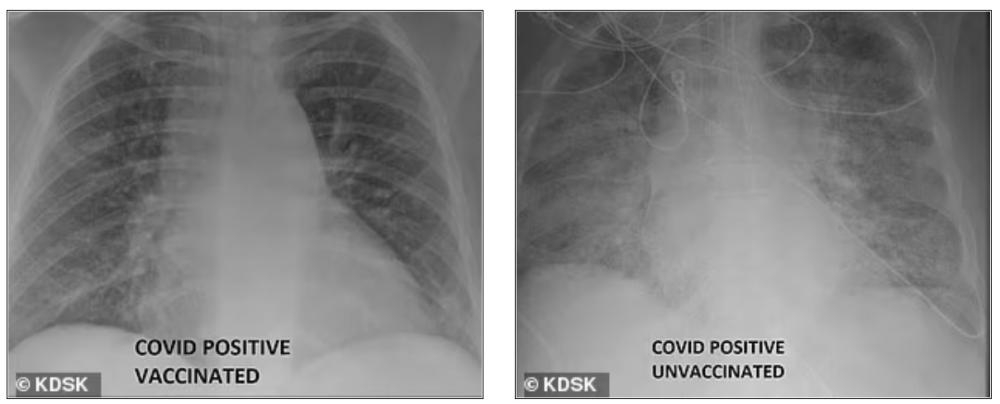

في هذا الإطار، نشر الدكتور غسان كامل، مدير وحدة العناية المركزة الطبية في إحدى مستشفيات سانت لويس، صورتين بالأشعة السينية لرئتين، إحداهما لمريض تم تطعيمه بفيروس (COVID-19)، والآخر لمريض (COVID-19) غير محصن.

وأظهرت الصور أن الأشعة السينية للمريض الذي تم تطعيمه، تحتوي على قدر كبير من المساحة السوداء، مما يدل على أنه كان قادرًا على استنشاق كميات كبيرة من الأكسجين، بينما تبدو الأشعة السينية لمريض (COVID-19) غير الملقح بيضاء بالكامل تقريبًا، فيما يُعرف باسم عتامة الرئة.

وتشير عتامة الرئة عادةً إلى أن الرئتين ممتلئتان بأشياء مثل السوائل أو البكتيريا، وتظهر على الأرجح شخصًا يحتاج إلى عناية مركزة. وغالبًا ما يؤدي فيروس كورونا إلى مضاعفات مثل الالتهاب الرئوي، والذي يحدث عندما تمتلئ الرئتان بالسوائل وتصبح ملتهبة، مما يؤدي إلى ظهور أعراض مثل السعال وضيق التنفس.